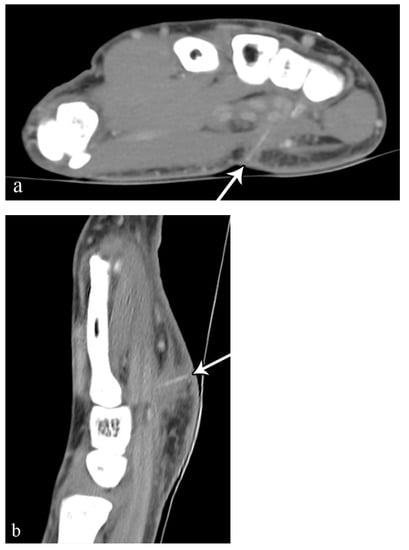

2.3. Soft-Tissue Foreign Body